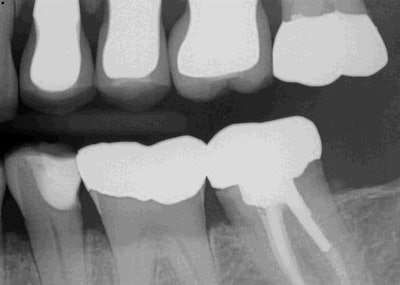

A 70-year-old man presented with a failing direct composite on tooth #20 with recurrent caries on the gingival margin. This tooth also presented as a "food trap" issue for the patient. Upon clinical and radiographic examination, it became apparent that the gingival margin was not restored properly on the existing distal-occlusal lingual (DOL), which led largely to the failure of the composite.

The preparation was quite wide and extended slightly subgingival near the lingual portion of the preparation. The wide box, curving tooth, and subgingival extension of the preparation add to the complexity of predictably restoring these types of cases.

Surefil SDR (Dentsply Sirona) was then placed in the gingival 1-1.5 mm of the proximal box and cured, followed by three layers of Filtek Supreme (3M). Finally, the restoration was polished using a Meisinger polishing kit. Postop radiographs confirm the gingival margin.